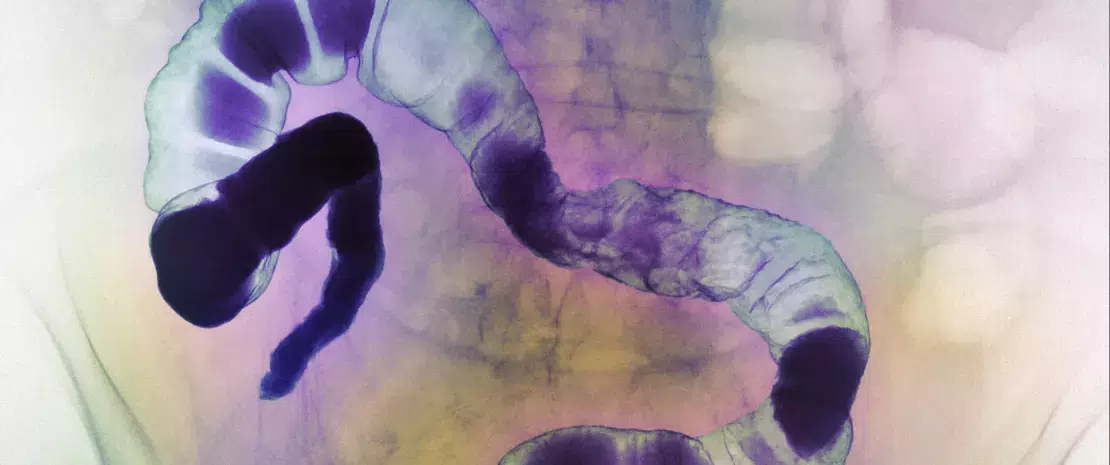

Existen pruebas cada vez más numerosas de que Fusobacterium representa una importante bacteria patógena intestinal asociada al cáncer colorrectal. Sin embargo, su papel en el cáncer colorrectal localmente avanzado, su destino después de una quimioterapia y su implicación en la evolución del tumor se desconocían hasta un reciente estudio retrospectivo que cuantificó F. nucleatum en el microentorno del tumor de 143 enfermos que recibieron una radioquimioterapia neoadyuvante (87 pacientes) o no (56 controles) antes de la escisión del tumor.

La visualización de F. nucleatum y su recuento por hibridación in situ demostraron que la bacteria se localizaba principalmente en la superficie luminal del tumor y que la radioquimioterapia reducía de manera significativa su cantidad: la densidad de F. nucleatum fue mucho más alta en los tumores no tratados que en los tumores tratados (mediana de la puntuación de 7,4 frente a 1,6), mientras que el 58% de los tumores fueron positivos para F. nucleatum en los controles frente al 26% en los pacientes sometidos a quimioterapia.